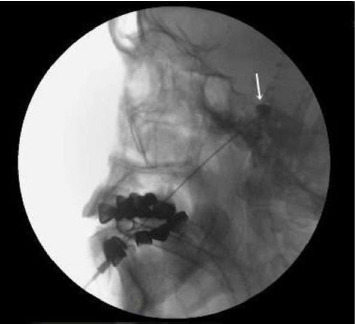

Abstract Image